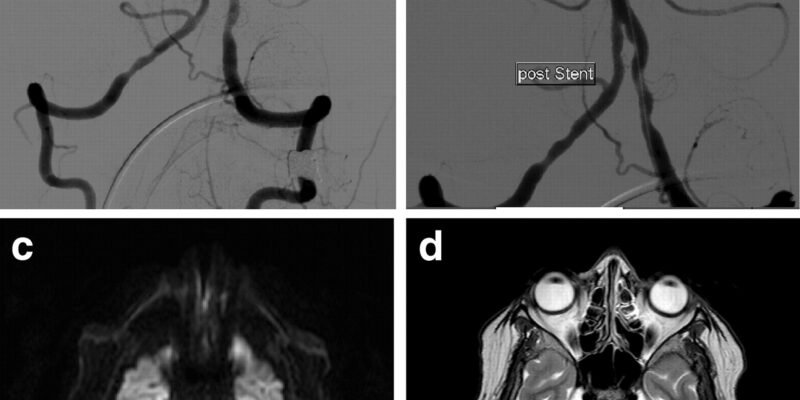

Before and After Pictures

A uterine fibroid embolization procedure is a minimally-invasive treatment option that can offer relief from abnormal uterine bleeding, cramping, and other symptoms associated with uterine fibroids. The procedure is performed by inserting a catheter into the uterus and delivering particles via an interventional radiology machine to block the flow of blood to the fibroid.

Uterine fibroid embolization is a relatively new treatment option for uterine fibroids. During the procedure, a catheter is inserted through the femoral artery in the leg and guided to the uterus by x-ray or ultrasound. The uterine arteries are then blocked with small particles that prevent blood flow to the fibroid, which eventually shrinks. This can be done as an outpatient procedure and side effects are minimal, though they may include some discomfort after or during the procedure or cramping afterward.